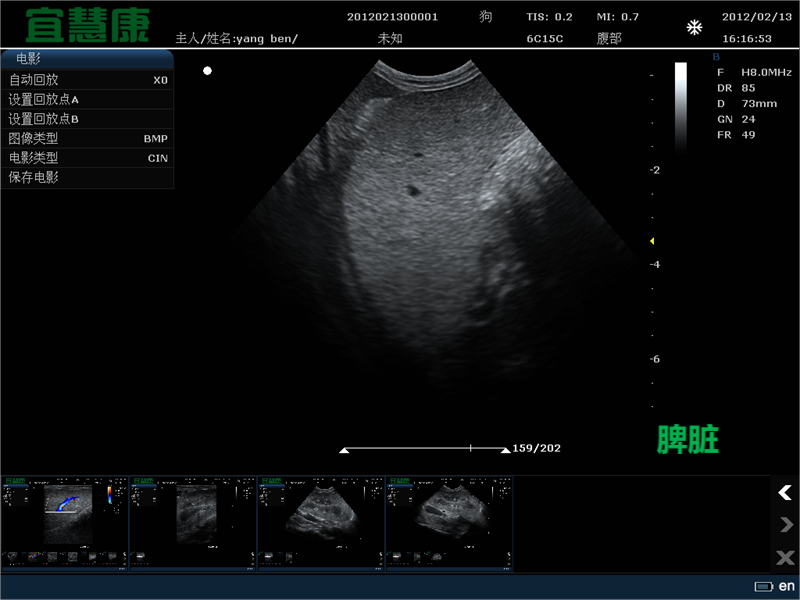

在兽医学中,微凸包和线性传感器目前被推荐用于LUS。在人类医学中,没有特定的先决条件。

长期以来,人们一直认为微凹凸或相控阵传感器是优选的,主要是因为它们的头部较小,使得检查在技术上更容易。他们也更善于观察更深的结构,但是胸膜线通常不太明显。因此,当胸膜线成像最重要时,推荐使用线性传感器。关于LUS的最小设备的第一个建议包括一个基本的超声设备,配备有频率为2.0-5.0 MHz的微凹凸或相控阵换能器。

在过去的十年中,这些建议已经改变,传感器的类型取决于它们所用于的医院部门。在重症监护病房,通常建议使用5.0 MHz微凹凸探头。如今,超声机器通常默认配备所有三种类型的换能器。这样既可以在危急情况下(没有时间切换传感器时)进行检查,也可以在病情稳定的患者身上进行常规LUS检查。当患者病情稳定时,建议使用微凸面、相控阵和线性传感器,以获得最佳质量的图像或检测尽可能多的细节,这在仅使用一个探头的检查中是不可能的。